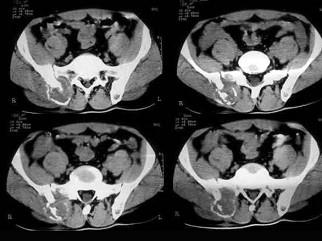

问题 患者 女,53岁,1个月前无明显诱因右髂部疼痛,为持续性隐痛,进行性加重,右下肢活动受限两周,体检右髂前上棘内侧可触及一3.0cm×2.0cm大小肿物,质韧,无活动,实验室检查无特殊,请结合所提供的图像,选择最佳选项 ( )

选项 A、髂骨纤维组织细胞瘤 B、骨母细胞瘤 C、骨髓炎 D、内生软骨瘤 E、骨结核

答案 A